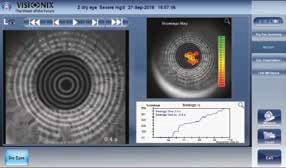

Has establishing a dry eye clinic been on your ‘to do’ list for some time now?

If the answer is a resounding ‘YES’ then you are not alone and this year’s Independents Day is definitely for you! This year’s programme is focussed on the pros and cons of commercialising dry eye services. The programme will be thought provoking, delivering useful tips and great ideas from top speakers who have ‘walked the talk’.